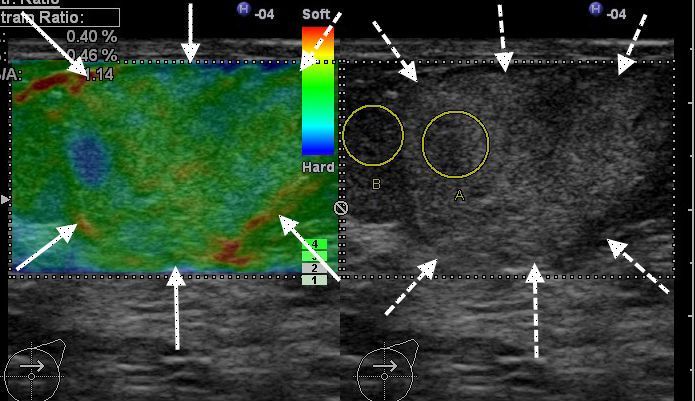

Исследование молочных желез и лимфатических узлов

Рак молочной железы занимает второе место среди онкологических заболеваний. За последнее десятилетие было проведено немало различных исследований по изучению способов диагностики рака молочных желез. Такой метод, как эластография, появился сравнительно недавно, но уже зарекомендовал себя с наилучшей стороны для подобной диагностики.

В комплексе с рентгенографией и ультразвуковой маммографией эластография позволяет не только выявить само новообразование, но с высокой точностью определить его природу. Например, дифференциальная диагностика между кистой с плотным содержимым и раковой опухолью достаточно сложна. Но определяя эластичность патологического очага, можно значительно снизить долю необоснованных пункций, а также определить долю пациентов, которые нуждаются в динамическом наблюдении и регулярном обследовании. Тот же самый принцип применим и к исследованию лимфатических узлов для выявления метастазов.

Эластография уже официально включена в международную шкалу BIRADS, которая является наиболее авторитетной в мире в области диагностики образований молочных желез.

Липома молочной железыЛипома молочной железы

Рак молочной железыРак молочной железы